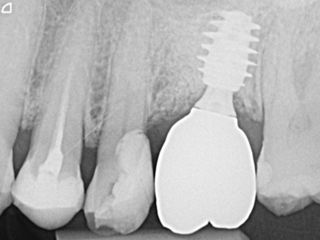

Dr. Andreas BENECKE, Germany In this case a GBR/GTR procedure was performed after extraction. Therefore, the bone situation can be challenging and is usually not a D1 bone situation. Read more